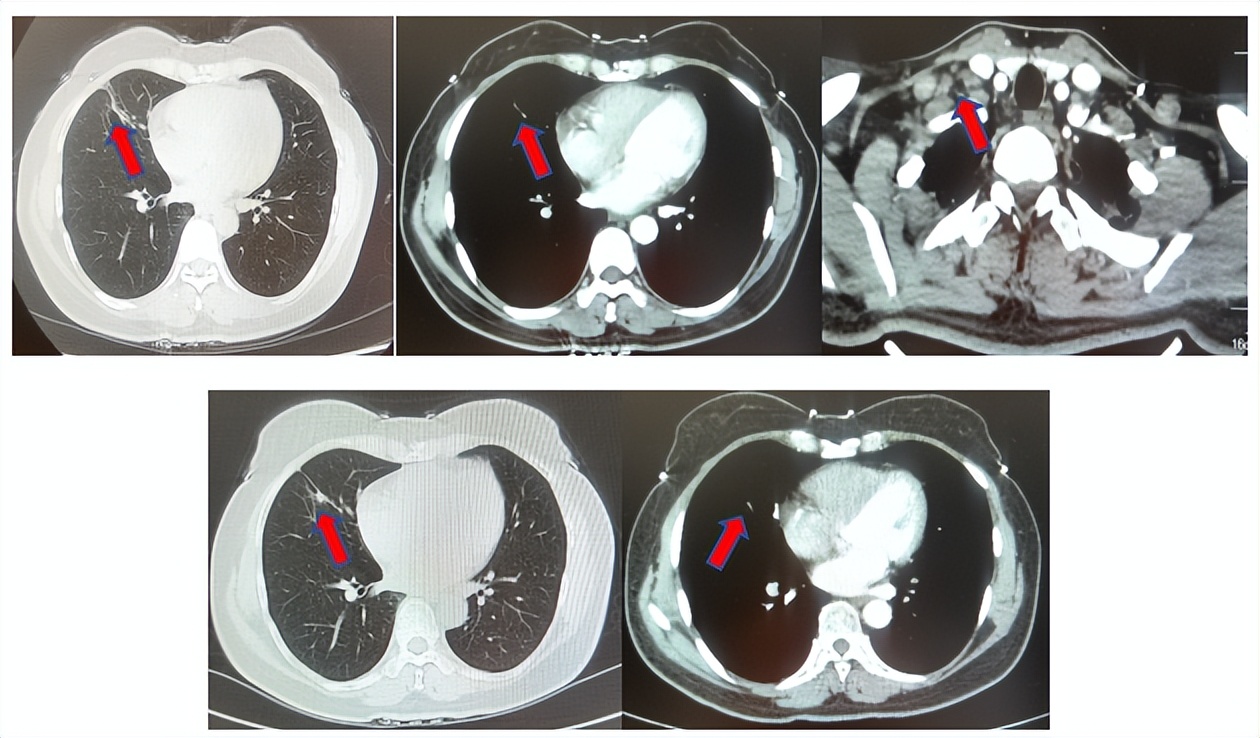

1.2影像学检查(图1)

肺+全腹CT:右肺下叶占位、伴纵隔多发淋巴结肿大,恶性可能性大;右侧心膈角结节,左侧胸廓入口淋巴结增大。

脑MRI:左侧顶叶及右侧小脑结节,转移可能性大。

图1:上两图分别展示基线肺CT肺窗及纵隔窗影像,下三图表示脑MRI影像。红色箭头指示病灶位置,分别为右肺肿物、右侧肺门转移病灶、左侧顶叶病灶、右侧小脑病灶及冠状面上的颅内两个病灶。